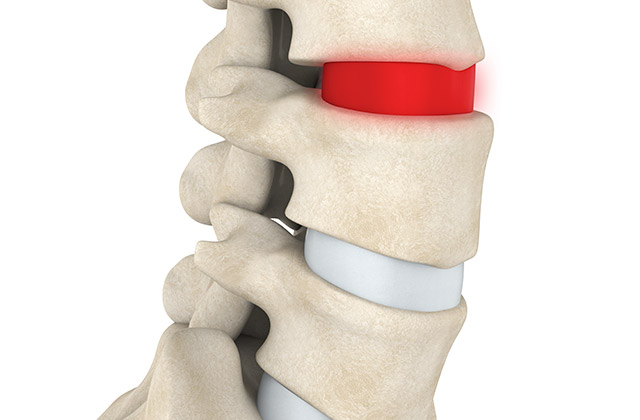

Disc Bulge

Everyone has heard the age old ‘I’ve slipped a disc’, but what does that really mean? Discs are the spongy cartilage between the spinal bones. Disc problems can vary from a slight bulge to a protrusion to a sequestration. All these terms describe the disc material entering the nerve or spinal cord canal, in different ways, which have different clinical outcomes. Patients can experience moderate to extreme pain, numbness, tingling in the arms and legs, great difficulty getting comfortable and pain that won’t ease in any position. Conservative management (like chiropractic treatments) can be very effective for the right cases while some cases need medical intervention. Rest assured you will be directed to the right treatment.